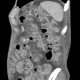

CT shows marked enhancement of the inner layer of colonic wall, edema of bowel wall - both small and large bowel, massive dilatation and tortuosity of mesenteric veins with shunting due to occlusion of superior mesenteric vein. Note also the presence of ascites and decreased density of liver parenchyma due to steatosis.